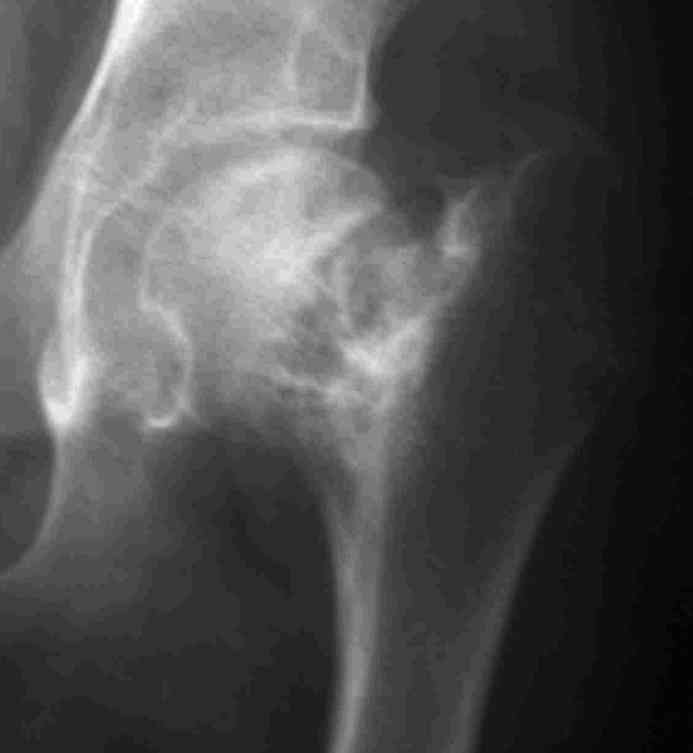

ВН>> Подросток 14 лет получил патологический перелом шейки левого бедра

ВН>> месяцев выполнить коррекцию ШДУ, что частично устранит

Интересует возможность одномоментного устранения очага ФД и корригирующей остеотомии, хотя я склоняюсь к двухэтапной тактике.Когда я впервые увидел этого подростка, сразу после снятия гипсовой повязки, консолидации не было и в планах была экскохлеация с медиализирующей вальгирующей остеотомией. Сейчас, когда консолидация отчетливая, возможно ограничимся только вальгизацией.На мой взляд надо оствить приемлемые условия для последующего ТЭП. Удивляет столь закрепившееся в практике мнение о возможности спонтанного восстановления костной после патологических переломов при кистах и ФД.

Около 16 лет наблюдаю пациента с ФИБРОЗНОЙ ДИСПЛАЗИЕЙ левой нижней конечности, полиосальная форма. Прилагаю рентгенснимки.